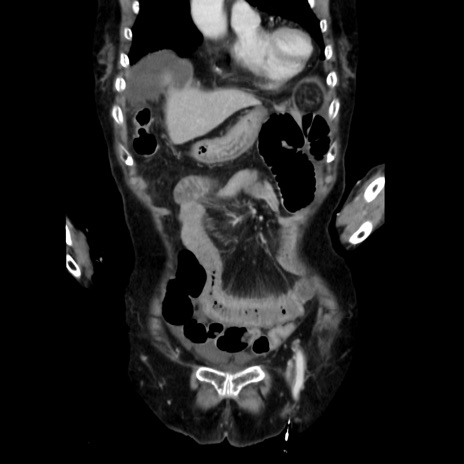

症例40(冠状断像)

【症例】90歳代女性

【主訴】腹痛・嘔吐

【現病歴】 食欲低下、嘔吐があり昨日他院受診。肺炎と診断され入院となる。入院後より腹部全体に圧痛あり。胃管留置され経過みていたが、症状持続するため、

当院転院となる。

【既往歴】胸椎圧迫骨折、胆石症

【身体所見】腹部:中央に激痛あり、圧痛あり、反跳痛不明

【データ】WBC 17100、CRP 18.82

矢状断像